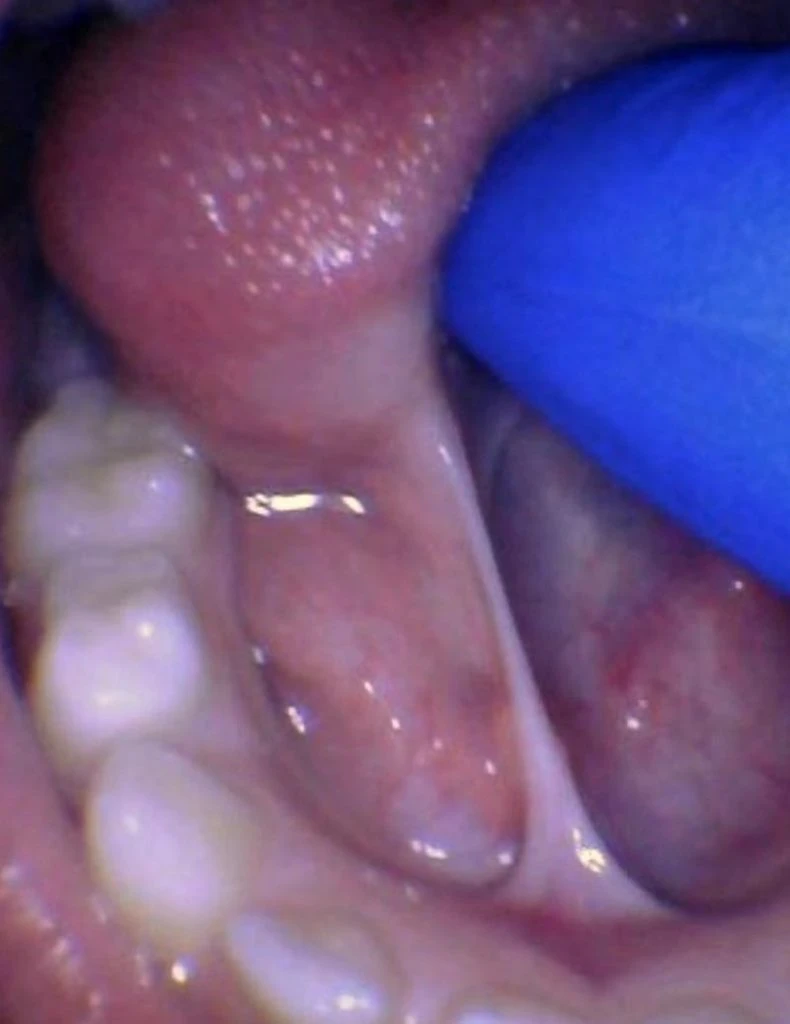

These images show the spectrum of tongue restriction in an infant.

View tongue restrictions